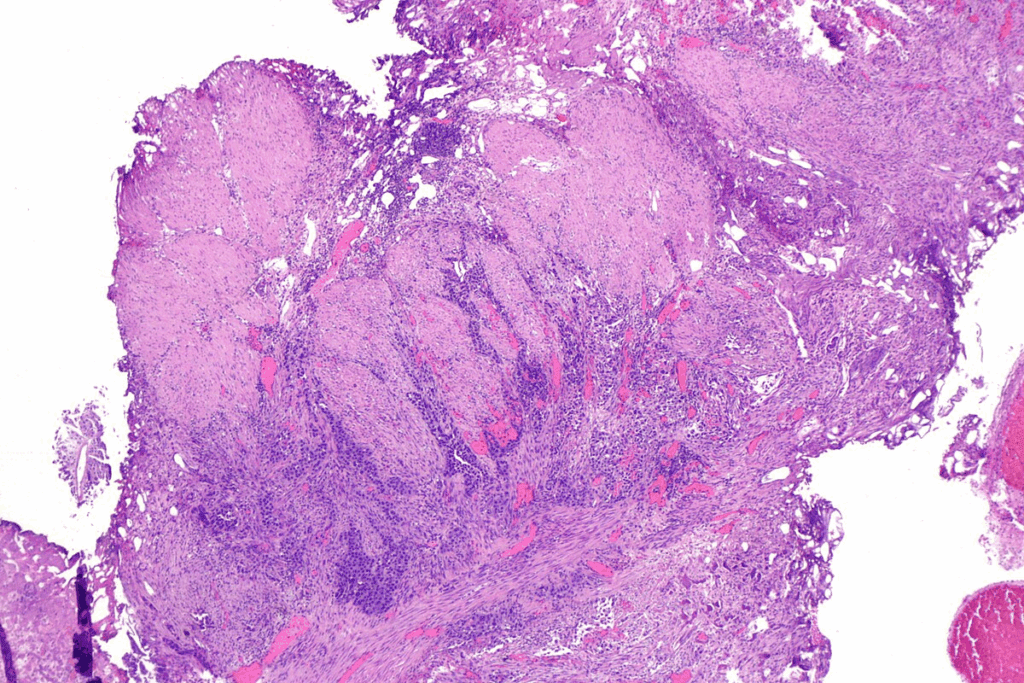

Understanding the Bladder Polyp Biopsy Procedure

A biopsy is often the best way to find out if bladder polyps are harmless or cancerous. This procedure is key for doctors to know what polyps in the bladder are. It helps them decide on the right treatment.

The Role of Cystoscopy in Diagnosis

Cystoscopy is a big part of the bladder polyp biopsy. It uses a thin tube with a camera to look at the bladder lining. Doctors can spot any areas that need a biopsy.

Cystoscopy Procedure: We use a cystoscope to see inside the bladder. The cystoscope has a camera that shows images on a screen. This lets us see the bladder lining clearly.

How Tissue Samples Are Collected

After finding suspicious areas, we take tissue samples. We use special tools through the cystoscope to do this.

These samples go to a lab for examination. They look at the tissue under a microscope. This checks for any abnormal cell growth or cancer.

Types of Biopsy Techniques

There are many biopsy techniques, depending on the polyps. The choice depends on the size and look of the polyps.

Biopsy TechniqueDescriptionAdvantages

Cold Cup BiopsyUses a special tool to remove tissue.It’s minimally invasive and precise.

Loop BiopsyUses electricity to remove tissue.Good for bigger polyps, can treat and diagnose.

Transurethral Resection of Bladder Tumor (TURBT)Removes the tumor and some bladder wall.It’s both diagnostic and therapeutic, giving detailed samples.

Knowing about the bladder polyp biopsy can ease worries. It explains cystoscopy, how samples are taken, and the biopsy types. We aim to make the process clear and reassuring for patients.

The Laboratory Analysis Process

The lab checks your biopsy sample carefully. Pathologists look at the tissue under a microscope for any odd cell growth or cancer. They stain the samples to see the cells better and compare them to normal bladder tissue.

The pathologist will say what kind of bladder cancer you have and how deep it is. A leading medical expert says,

“The accuracy of the biopsy results is key for choosing the right treatment.”

Understanding Pathology Reports

Your pathology report gives detailed findings from the lab. It tells you about the cells, if there’s cancer, and its grade and stage. Knowing this report helps you understand your diagnosis.

• The type of cells found (e.g., urothelial, squamous)

• If there’s cancer and if so, its presence

• The cancer’s grade (how much it looks like normal cells)

• The cancer’s stage (how far it has spread)